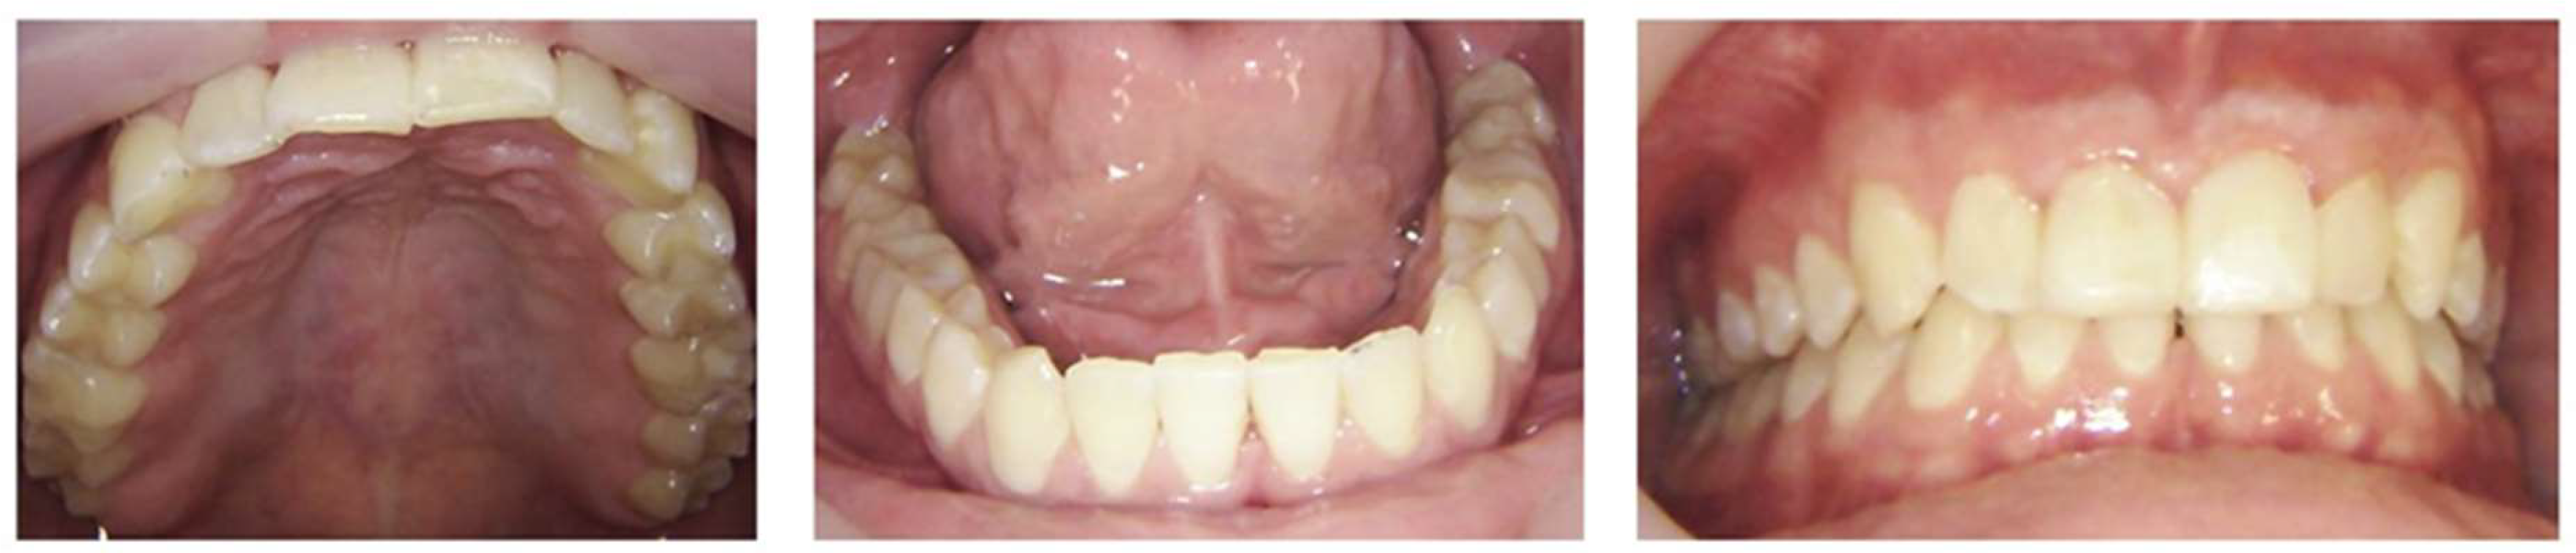

A comprehensive oral examination, including intraoral photographs and full-mouth radiographs (Figure 1 and Figure 2), was conducted. The examination revealed that the patient had a full set of 32 teeth. Among these, 25 teeth exhibited active decay affecting single and/or multiple surfaces, six had incipient carious lesions, and one tooth was sound. Fractures were identified on the incisal surfaces of teeth numbered 41, 31, and 32. Furthermore, the distal-occlusal lingual wall of tooth 46 was found to be fractured, and tooth 28 exhibited extrusion.

Figure 2. Pre-treatment radiographs.